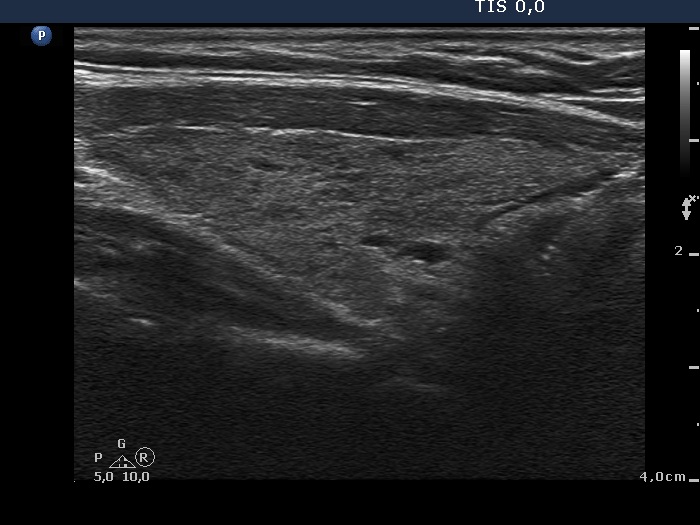

Ultrasonography: The thyroid was minimally-moderately hypoechogenic and presented fibrosis. There was a cystic lesion in the lower dorsal part of the right thyroid bed.